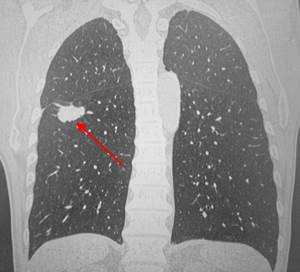

1) Аденокарцинома - выявляется приблизительно в 35% всех случаев. Чаще всего это периферическая опухоль, выглядящая как одиночный (солитарный) узел различных размеров с типичными признаками злокачественности, с наличием спикул - лучистых краев, которые образуются за счет прорастания рака по лиматическим сосудам; участков некроза, распада и кровоизлияний в строму опухоли. Аденокарцинома часто и рано метастазирует. Прогноз очень вариабелен, во многом он зависит от того, насколько рано было обнаружено образование.

Периферический рак легких на КТ выглядит как очаг либо узел, расположенный на периферии органа вдалеке от корня. Обычно он имеет однородную структуру, в некоторых случаях с участками некроза, обызвествлениями и кровоизлияниями в паренхиму. Края типичной раковой опухоли неровные, с множественными «спикулами» за счет лимфангиита. При расположении вблизи плевры образование деформирует ее и подтягивает к себе. Размеры его различны - от очага (3-10 мм) до узла (10-50 мм и больше).

Типичный периферический рак легкого (аденокарцинома) на МСКТ. Справа в 6 сегменте легкого выявлен плотный мягкотканный узел со спикулами, деформирующий и подтягивающий к себе междолевую плевру.